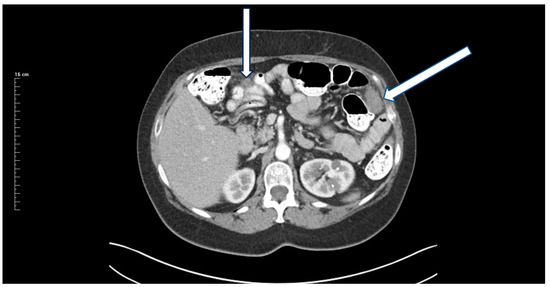

13 December 2017: Preoperative CT showed an 8 cm mass (Figure 1).

Figure 1. CT of a right-sided primary colonic mass that measures 8 cm in its greatest dimension. The external surface of the mass is irregular, suggesting peritoneal thickening. The medial aspect of the mass abuts the duodenum and no fat plane separating the mass from the second portion of the duodenum is evident. The mass penetrates posteriorly toward the right common iliac artery without obvious obstruction of the right ureter. A fat plane between the posterior aspect of the mass and the psoas muscle is present. No obstruction or perforation of the bowel above the mass exist. A single 1.5 cm lymph node is enlarged at the medial aspect of the mass. No additional systemic or local–regional manifestations of the cancer are evident. Radiologically, the mass is staged as T3/T4, N1, M0 with transmural extension through the wall of the intestine.